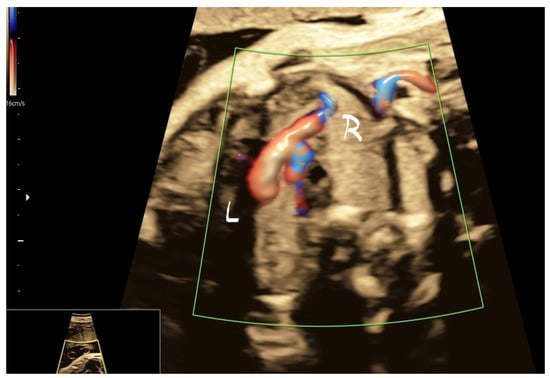

4.3. Case 3